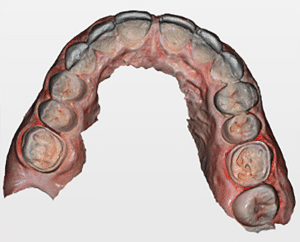

Le mock-up antérieur est toujours en bouche. On demande au logiciel de dupliquer notre empreinte de référence et on vient couper sur le duplicata les secteurs postérieurs. On scanne ensuite les préparations et notre empreinte de travail est finie. Le logiciel permet de vérifier les épaisseurs de préparation en cas de doute. L’empreinte (Fig.8a, b, c et d) est envoyée au laboratoire, le mock-up retiré et la patiente repart. Dans notre cas clinique, il n’est pas nécessaire de faire des restaurations provisoires postérieures car les tissus dentinaires exposés ont été hybridés puis protégés par du composite fluide et le reste des préparations est amélaire.

Fig.8a, b, c et d : Empreinte des préparations postérieures.

Fig.8b.

Fig.8c.

Fig.8d.